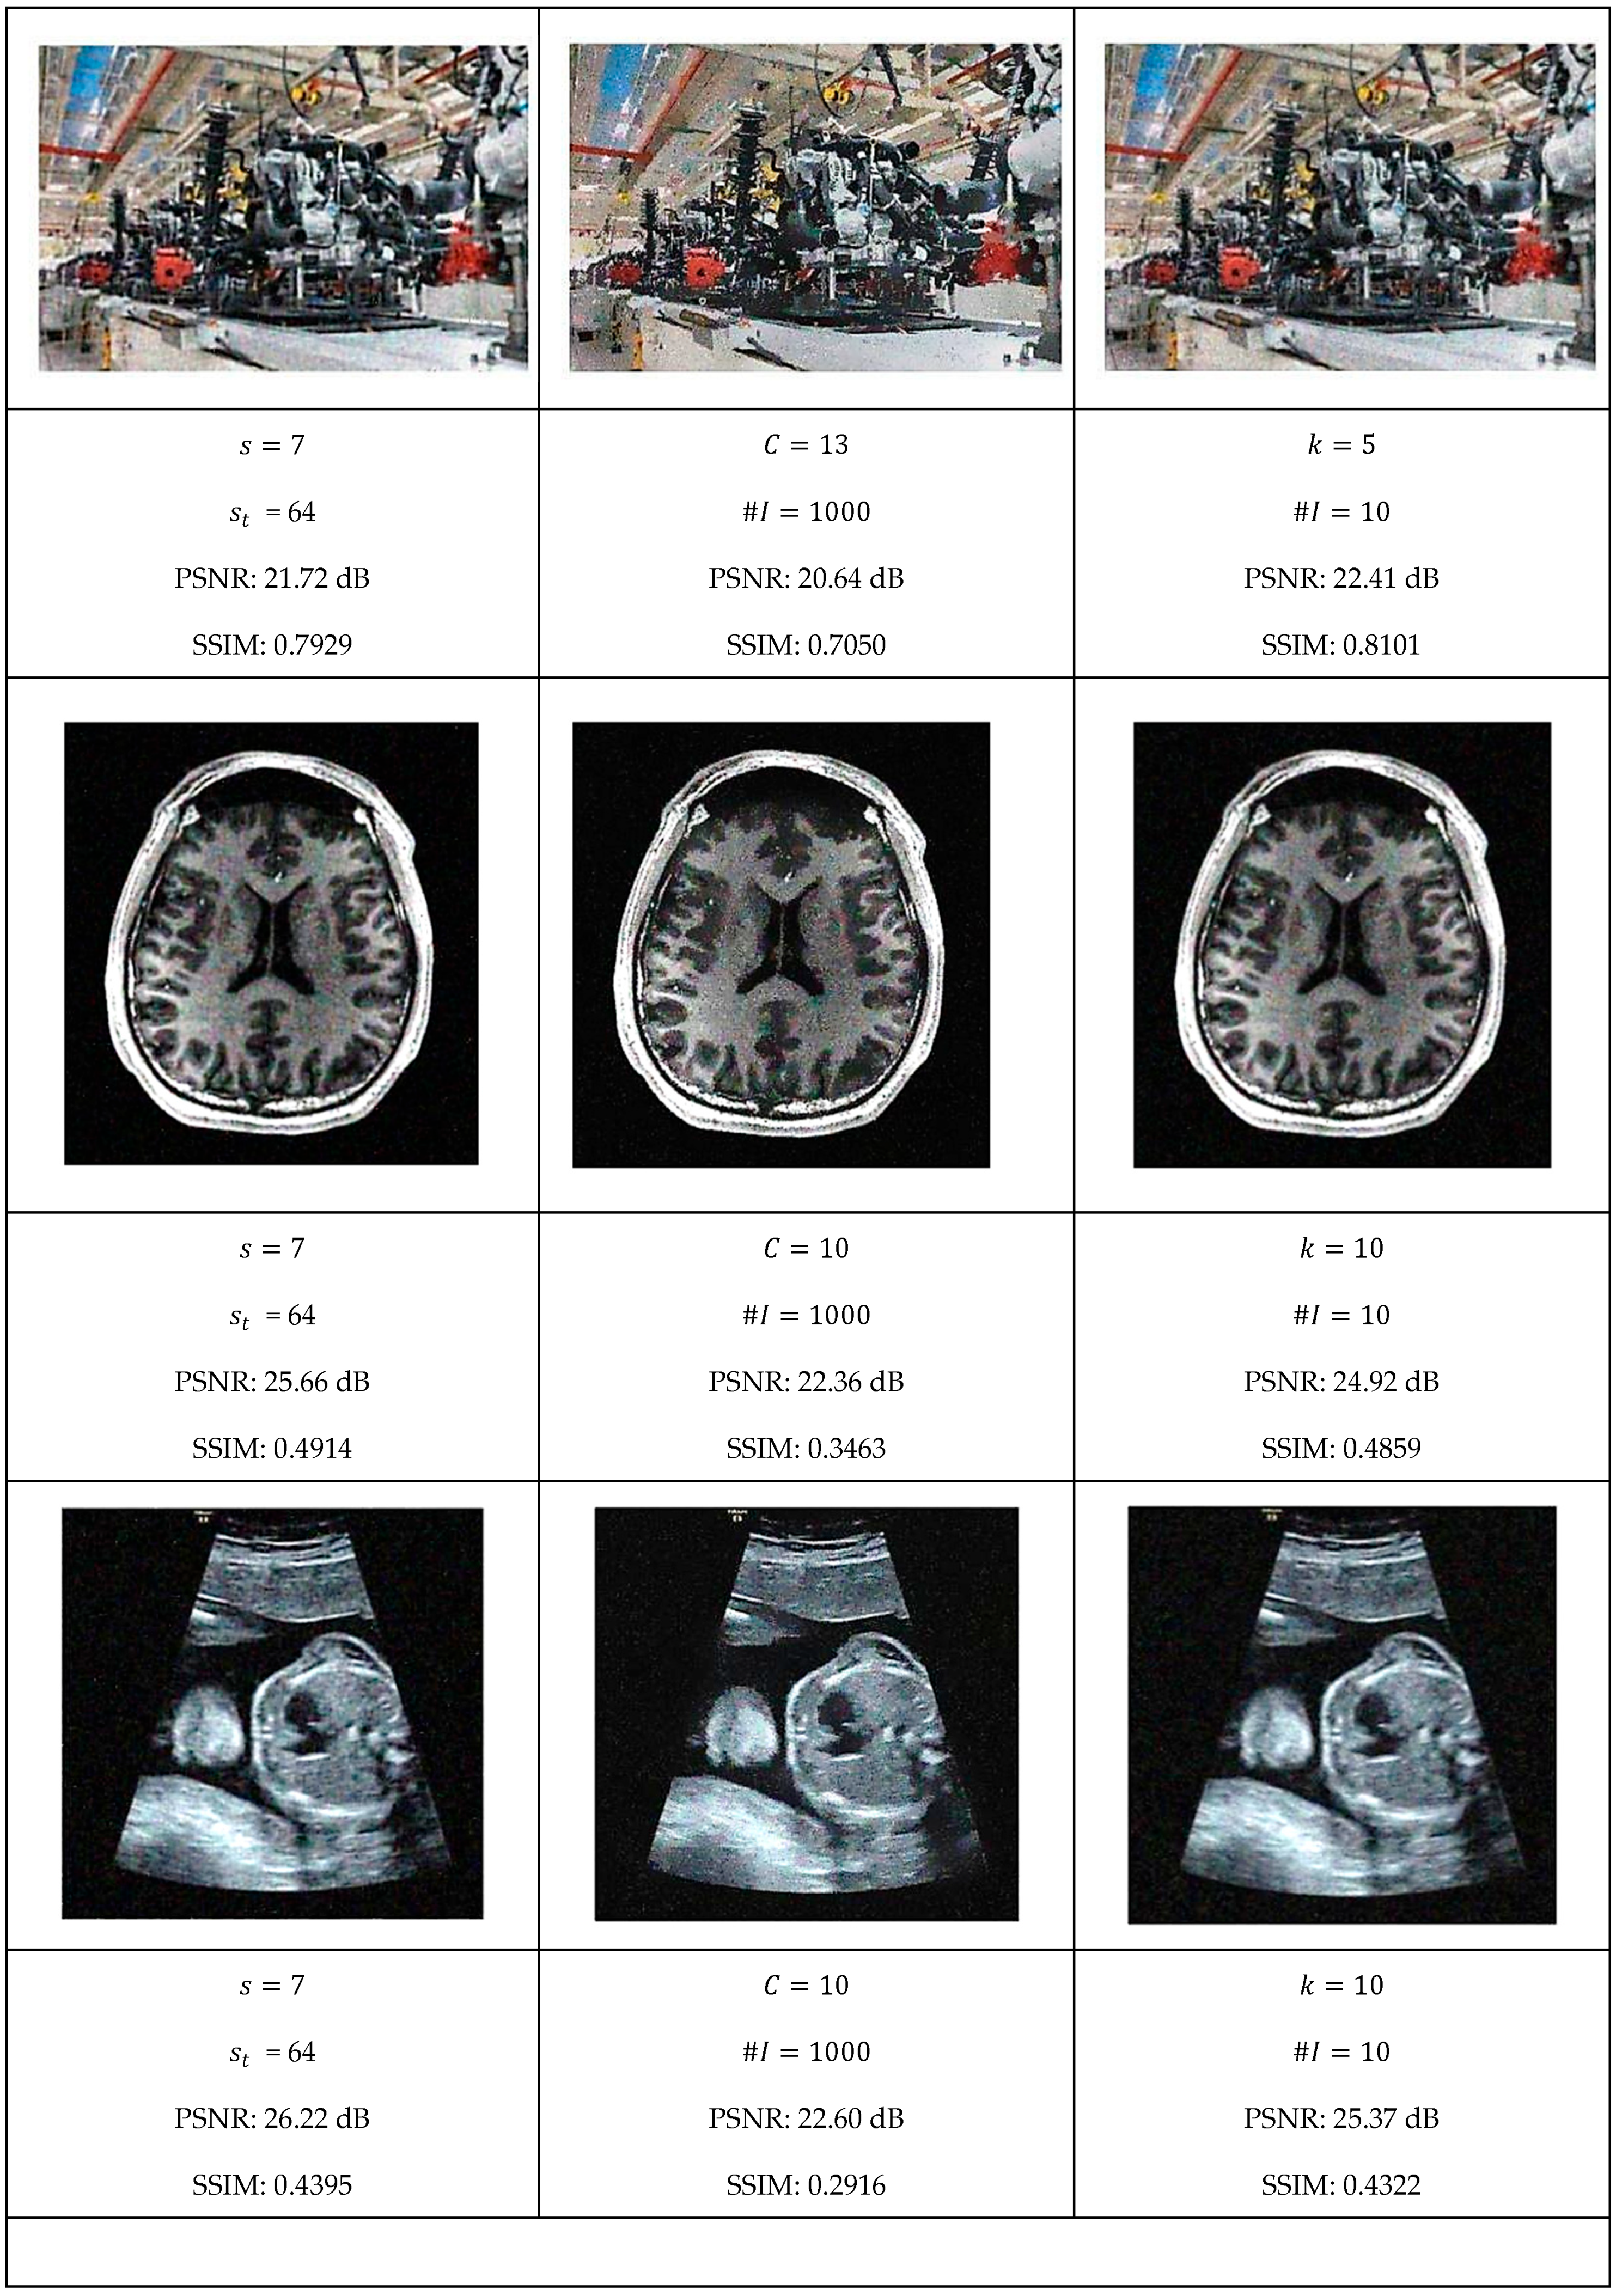

This section presents a comprehensive comparative analysis of our geodesic filtering approach against the state-of-the-art methods. The key to this comparison is based on PSNR and SSIM difference metrics. The noisy images shown in Figure 8 were processed using various implementations of the filtering algorithms described in Section 2. To be fair in our comparison, as with the geodesic filter, we tuned the parameters to produce the best PSNR value possible. The results of this comparison are collected in Figure 9 and Figure 10.

Figure 9.

Optimal filtering results for LMS, gradient anisotropic diffusion, and curvature anisotropic algorithms.

Each algorithm was carefully tuned to achieve optimal performance using the same test image database with standardized noise conditions. For each filter, the tuning parameters are as follows:

- Least Median Filter: window size and tile size ;

- Gradient Anisotropic Diffusion: conductance and number of iterations #I;

- Curvature Anisotropic Diffusion: the mean curvature of the level sets and number of iterations #I;

- Bilateral Filter: kernel size, spatial distance weight, and color distance weight;

- Gaussian Weighted Wavelet DIP Neural Network: Gaussian variance, minimum tile loss, tile size, and tile overlap size.